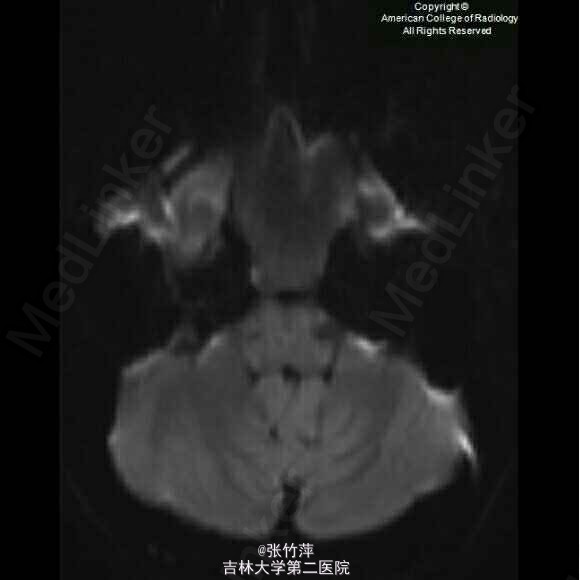

女,20岁。头痛一月余,伴复视,流泪,视力下降。

脑部磁共振图片如下

蝶窦粘液囊肿